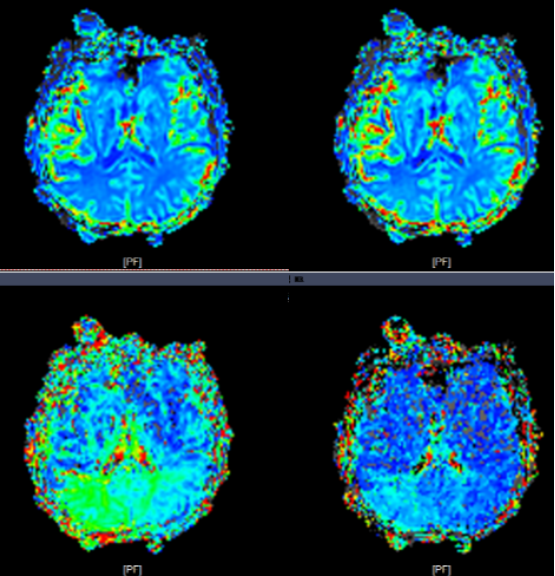

患者为一名65岁男性,3月16日突发左侧肢体活动障碍,次日症状加重,并出现反应迟钝、言语不清、口角歪斜等新发症状后转至苏大附四院继续治疗。入院后CTA(CT血管造影术)检查提示右侧大脑中动脉水平段(R-M1)管腔完全闭塞,远段分支稀疏;CTP(脑灌注检查)则提示右侧额顶颞叶缺血性灌注异常;头颅MRI(核磁共振成像)见右侧岛叶、颞叶、右侧脑室旁及放射冠区急性脑梗死。综合检查结果,考虑到患者发病时间较长,与家属商议后予以强化内科治疗。

CTA+CTP:右侧大脑中动脉水平段(R-M1)管腔完全闭塞;右侧额顶颞叶缺血性灌注异常

术前PWI:右侧岛叶、颞叶、右侧脑室旁及放射冠区CBF、CBV减低,MTT、TTP较对侧延长

术后PWI:右侧岛叶、颞叶、右侧脑室旁及放射冠区血流明显改善